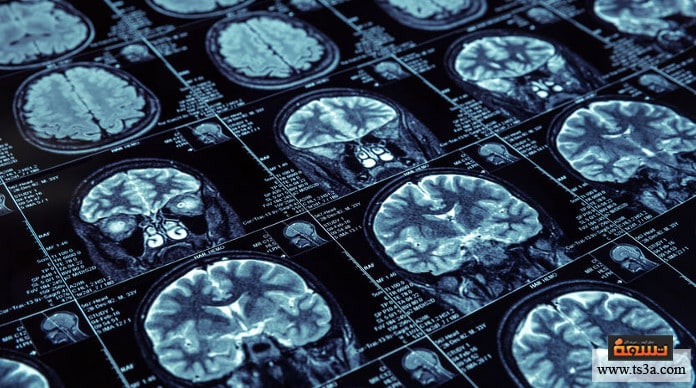

تأثير المغناطيس على الدماغ

يعتبر تعريض رأس الإنسان لمجال مغناطيسي من الطرق القديمة الفعالة في علاج الكثير من الأمراض المزمنة التي يفشل الطب الحديث في علاجها، وقد حدثت هذه الطريقة بأكثر من شكل، ويعتبر (التأثير المغناطيسي عبر الجمجمة) هو أشهر هذه الأشكال ويشتهر بعلاج (TMS).

وتتم هذه الطريقة في العلاج عن طريق تعريض جسم المريض لمجال مغناطيسي متغير فيمر بفروة الرأس ويولد بداخلها تيار كهربي مستحث، وبدأ استخدام هذا الأمر لقياس العلاقة بين الجهاز العصبي والعضلات الهيكلية، حيث كان باستطاعة الطبيب أن يعرف عن الكثير من الأمراض بهذا القياس مثل: السكتة الدماغية، وبعض الاضطرابات، والتصلبات.